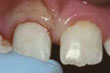

RepairedDintele fracturat după reconstrucţie

Dinte parţial fracturat: Dacă nu există durere şi fragmentul desprins este mic, puteţi decide singur dacă, cum şi când doriţi repararea lui. În funcţie de dimensiunea fragmentului desprins, dintele poate fi şlefuit sau corectat prin proceduri de cosmetică dentară. Alte opţiuni includ faţetarea, reconstituirea coronară şi obturaţia. Rugaţi medicul dentist să vă prezinte aceste soluţii. Dacă fractura s-a produs la suprafaţa unei obturaţii sau la un dinte artificial, se impune înlocuirea acestora.